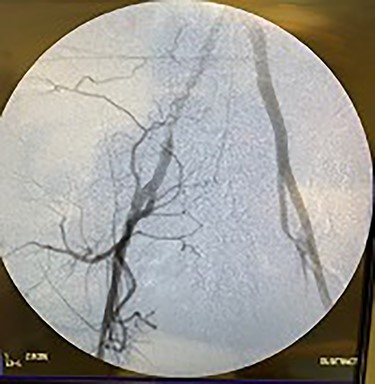

Catheter arteriogram results showed significant occlusion of the left iliac artery (Figs 3 and 4), the right iliac artery (Fig. 1), as well as the distal abdominal aorta (Fig. 2). There were numerous collateral vessels noted, indicating the presence of long-standing proximal stenosis (Fig. 1). The decision was made to use angioplasty to help widen the areas of stenosis. An 8 mm × 40 mm Passeo balloon was advanced from the right femoral artery into the left iliac artery (Fig. 7) and insufflated to 6 mmHg (Fig. 6). The balloon was allowed to remain expanded for 1 min and then was deflated. Next, the distal aorta was repaired in a similar fashion. The balloon was advanced into the distal aorta from the right femoral access and insufflated to 12 mmHg (Fig. 8). The balloon was allowed to remain expanded for 90 s.

Fluoroscopy of bilateral iliac arteries showing significant arterial disease.